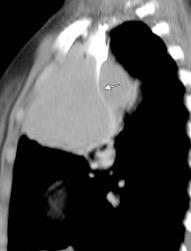

Visible en el adulto normal por interfase de la pared externa de la aorta con el aire del LII.

Causas de alteración

Normal

Patología aórtica Disección/ Aneurisma Úlcera ateroesclerótica

Adenopatías/ Ca. de Pulmón Hematoma Patología del LII

Marano R et al .Cardiac Silhouette Findings and Mediastinal Lines and Stripes. Chest 2011

Borramiento de la banda PARA-aórtica por AdenoCa. de LII, no visible en 2005

Borramiento parcial por Ca. epidermoide.